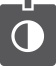

Aspect échographique du pole supérieur d’un thrombus (caillot de sang) dans la veine cave en arrière du foie